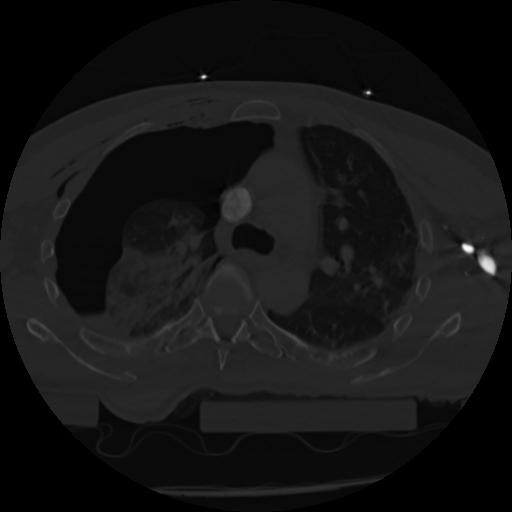

22 ANGIO,CE,Vol,0.5,ANGIO,,